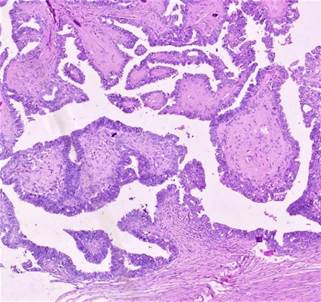

the surface. The microscopic examination showed papillary carcinoma with no

immature component (Figure 2).

Figure 2. Histopathology image [40 X magnification]

showing papillary thyroid carcinoma in a mature cystic ovarian teratoma.